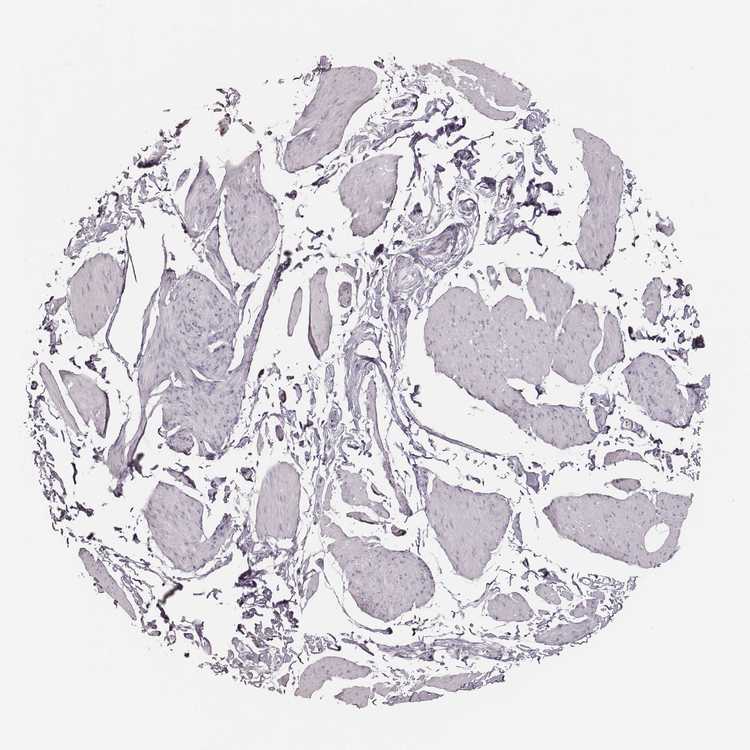

TISSUE PRIMARY DATA SMOOTH MUSCLE Show tissue menu

Smooth muscle

SMOOTH MUSCLE - Antibody stainingi

Antibody staining in the annotated cell types in the current human tissue is reported as not detected, low, medium, or high, based on conventional immunohistochemistry profiling in selected tissues. This score is based on the combination of the staining intensity and fraction of stained cells.

Each image is clickable and will lead to virtual microscopy that enables deeper exploration of all samples and also displays staining intensity scores, fraction scores and subcellular localization as well as patient and tissue information for each sample.

Antibody HPA026890

Smooth muscle cells Not detected